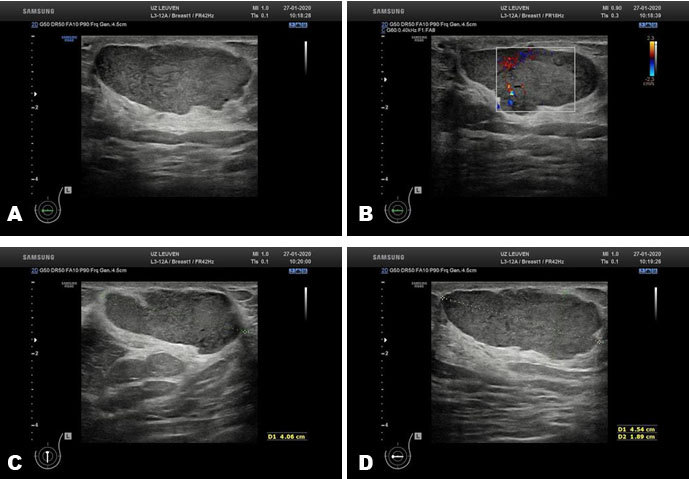

A 48-year-old woman presented at our institution with a palpable retro-areolar lump in the left breast. On clinical examination the lump was about 4–5 cm in size, painless, and without any skin changes or nipple retraction. No nipple discharge could be provoked. Right and left mammograms were obtained (Figure 1A, Figure 1B, Figure 1C, Figure 1D). Both breasts showed a breast imaging-reporting and data system (BI-RADS) density C. The right breast was normal. In the left breast, a mass in a retro-areolar location was visible. Other characteristics were an oval shape, high density, and circumscribed margins. Measurements were 44 × 24 × 41 mm. No calcifications or associated skin changes were seen. Additional ultrasound of the left breast showed an oval retro-areolar mass with parallel orientation in relation to the pectoral muscles (Figure 2A). The lesion showed overall circumscribed margins with a few angulations. Echo pattern was hypoechoic, with moderate internal vascularization on color Doppler and a few small cystic components (Figure 2B and Figure 2C). The lesion showed slight posterior enhancement. Measurements were 45 × 19 × 41 mm (Figure 2B, Figure 2C, Figure 2D). No axillary lymphadenopathy was identified. Due to age and the presence of a new palpable soft tissue mass additional, core biopsy (3 × 18 Gauge) was performed and BI-RADS 4a category was assigned.

Figure 2: Ultrasound of the left breast lesion. (A) Parallel oriented hypoechoic mass with circumscribed and few angulated margins. (B) Color Doppler showed moderate internal vascularization. (C, D) Measurements 45 × 19 × 41 mm. A few small internal cysts are visible.